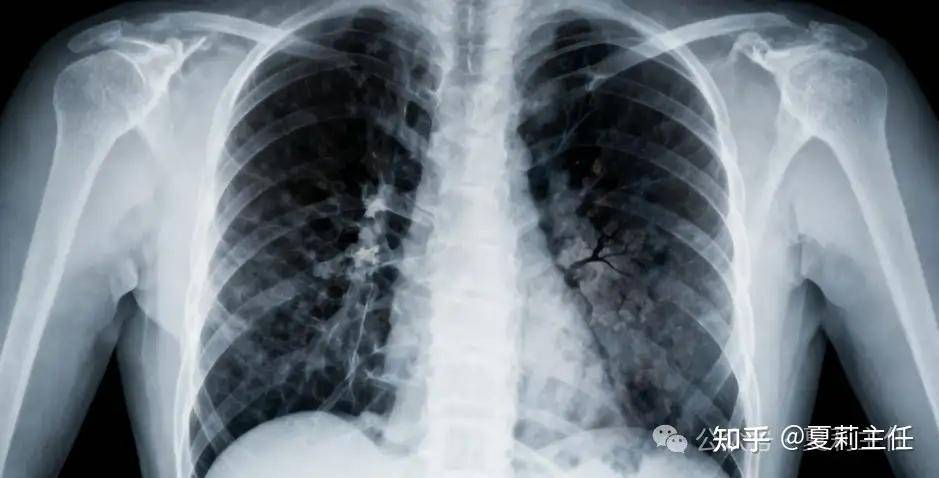

68岁的张阿姨(化名)经检查确诊为局部晚期非小细胞肺癌伴肋骨转移,剧烈骨痛让她连吞咽都困难。最爱韭菜鸡蛋饺子的她,绝望地问夏主任:“我是不是再也吃不上饺子,没多少日子了?”

非小细胞肺癌:最常见类型,生长慢、转移晚,精准治疗空间大,早期手术切除后5年生存率较高,中晚期以综合治疗为主。精准放疗像 “精准导弹”,能精准杀肿瘤、保护正常组织,适合骨转移等需缓解疼痛的患者,若基因检测发现特定突变,靶向治疗可 “精准打击” 且副作用更小,免疫治疗也为部分患者提供了新选择。